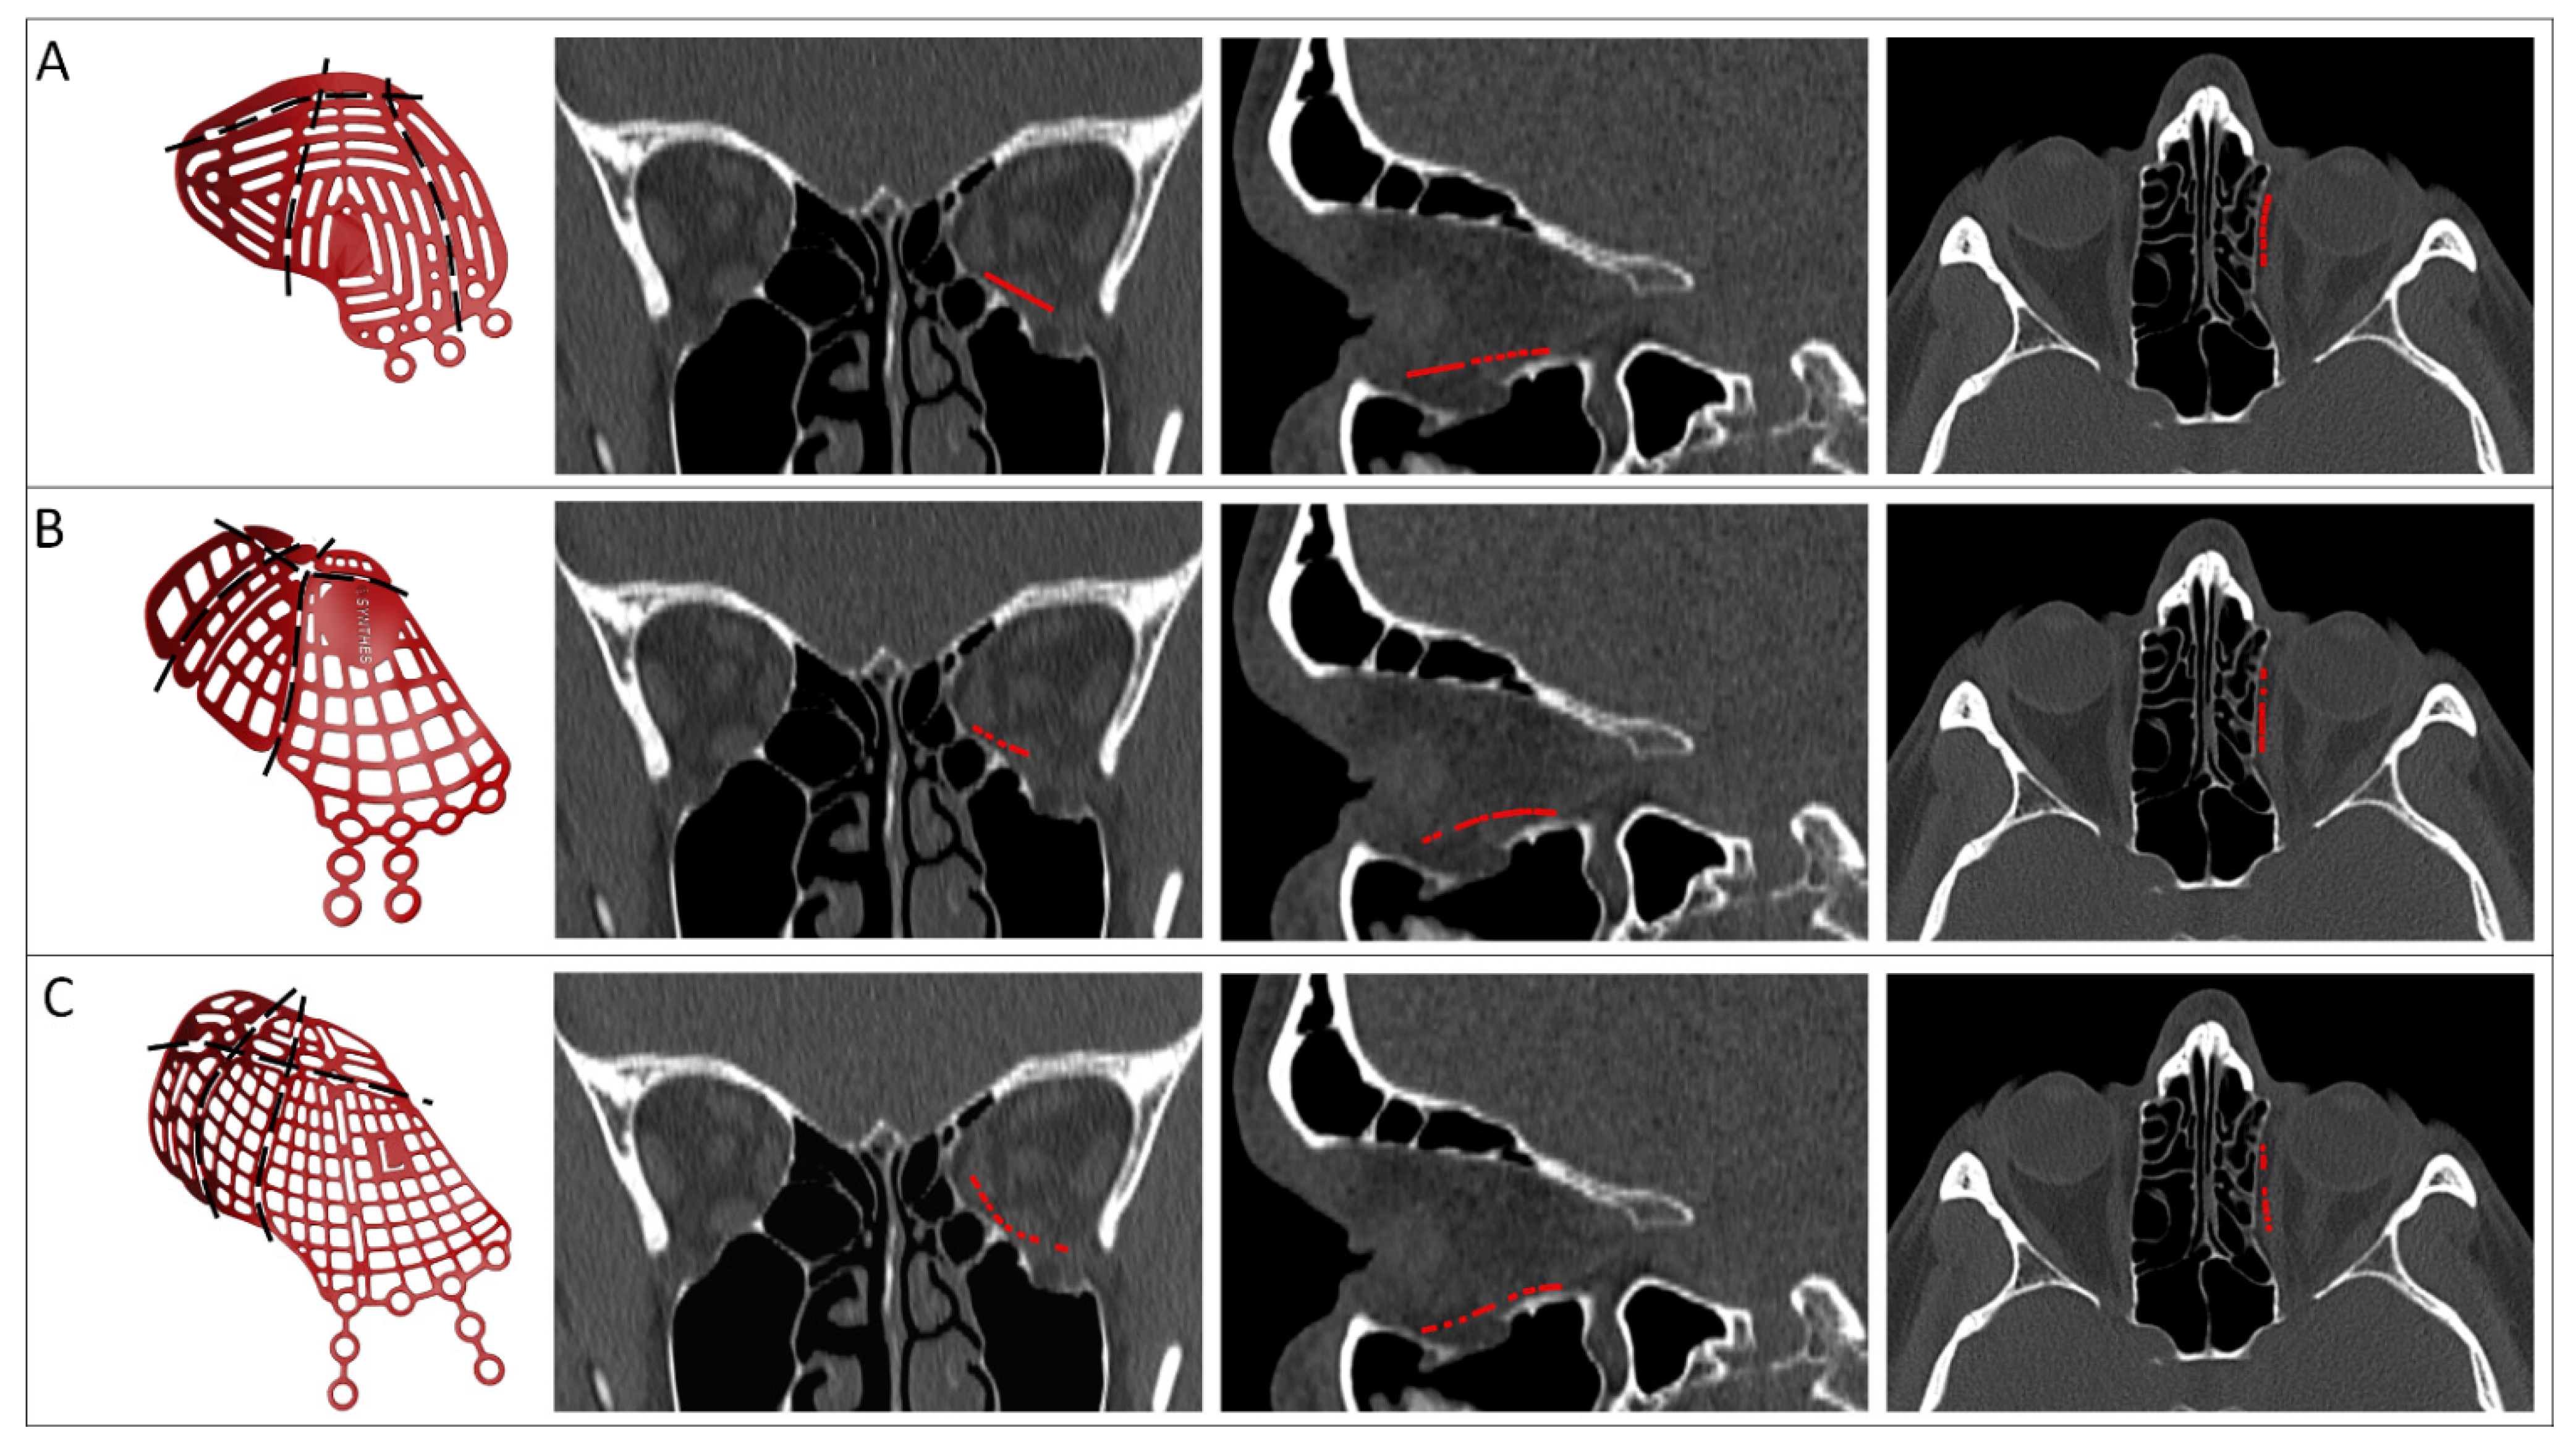

2.3. Virtual Surgical Planning